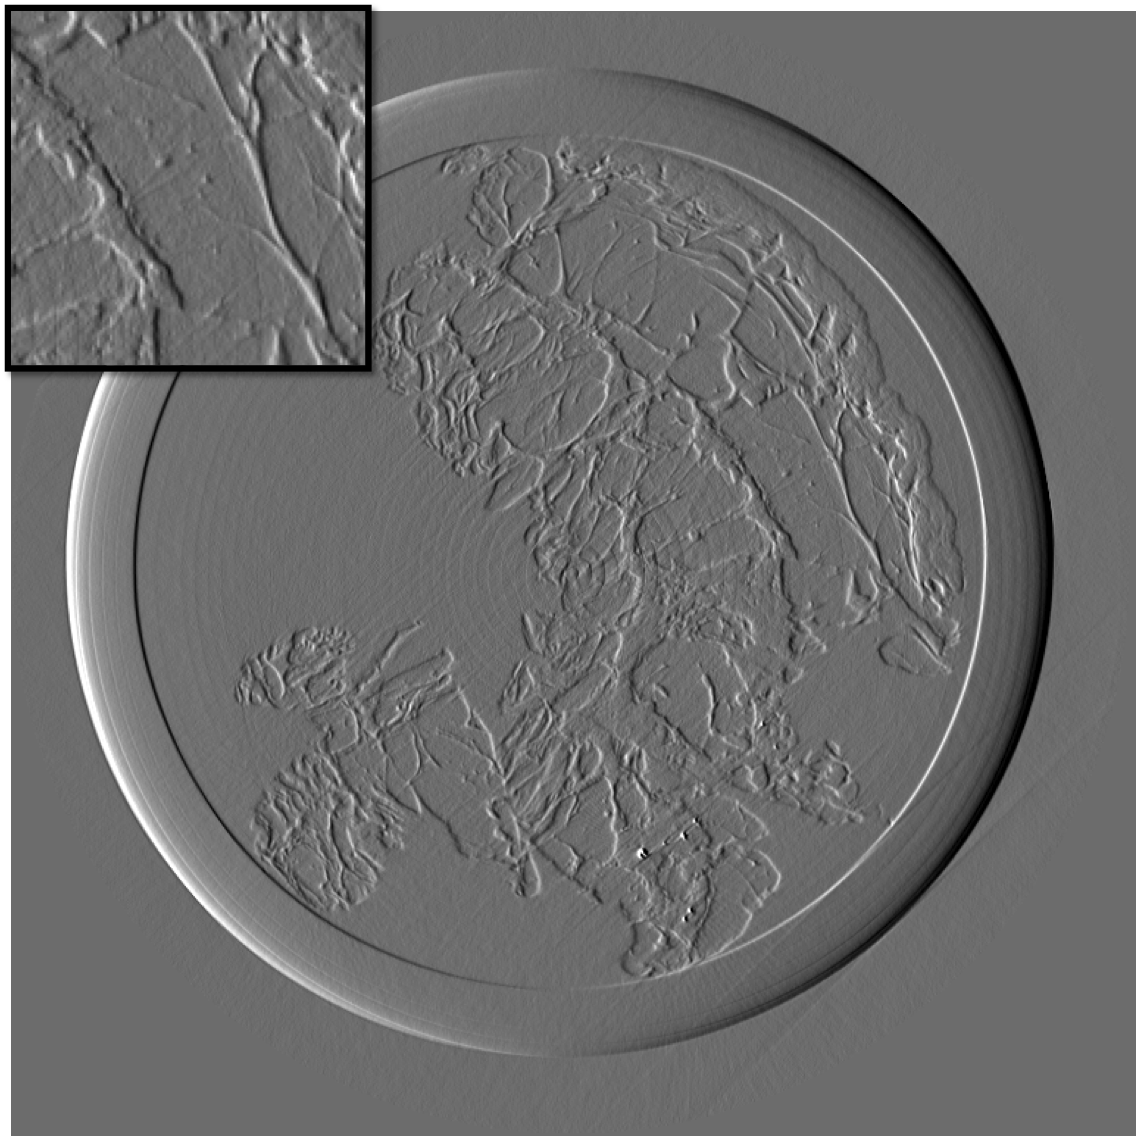

Figure 10 is the reconstruction for a pixels slice, using only 200 projections over the 1000 available. The upper left square is a zoom in the region marked in sub figure 10. The right column is the reconstruction with our method for X and Y components, while the left column is reconstructed with standard filtered back-projection using all 1000 available projections. Using our method we can still generate a high quality image with only one fifth of the projections which would be otherwise necessary to generate a high quality reconstruction with the standard FBP method. Visually the difference between the FBP results obtained with full data set and our method with a five-fold reduction of data is barely noticeable. The different borders of structures like skin layers, fatty tissues, and collagen strands are easily identified. The obtained result are very promising and a systematic evaluation for clinical application is under-way. The radiation dose absorbed by the sample during 200 projections is comparable to that of a standard clinical dual view (2D) mammography (3.5mGy).

For an eventual future clinical application of the PCI method it is important to investigate which is the acceptable compromise in terms of low dose and sufficient level of image quality. We need therefore to better explore how the quality of the reconstruction is degraded when we reduce the dose (i.e. number of projections and the acquisition time) further below the standard values. To this end, we performed a reconstruction with only 125 projections and results are shown in the figure III-D for one gradient differential image.

For an eventual future clinical application of the PCI method it is important to investigate which is the acceptable compromise in terms of low dose and sufficient level of image quality. We need therefore to better explore how the quality of the reconstruction is degraded when we reduce the dose (i.e. number of projections and the acquisition time) further below the standard values. To this end, we performed a reconstruction with only 125 projections and results are shown in the figure11. The first column present the result using our method, the second column is the result of reconstruction using FBP algorithm.

If a slightly higher noise level is tolerable, the method may be used with very few projections and thus applied to the screening and diagnosis of human breast cancers with an even lower radiation dose than conventional dual mammography. The results of our reconstruction show an image quality and a capability of discriminating fine structures that are still clinically acceptable. On the contrary, images produced with the standard FBP reconstruction method are very noisy and not diagnostically satisfactory.